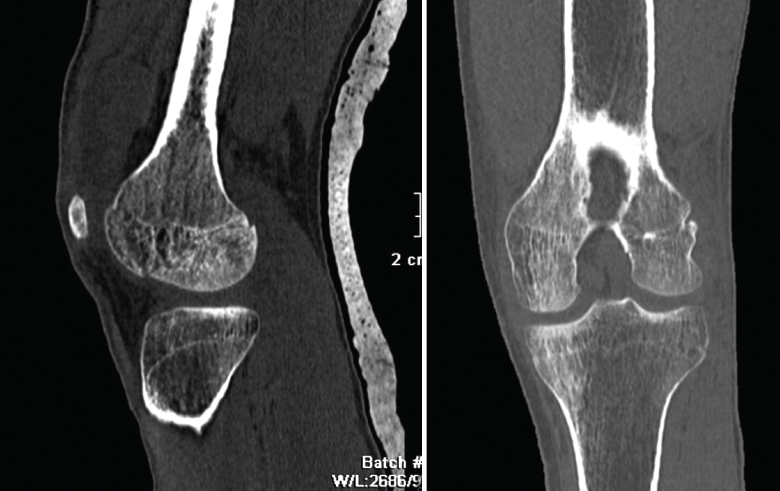

Figura 19. Corte de reconstrucción sagital y coronal de tomografía axial computarizada de rodilla: fractura de Hoffa del fémur, del cóndilo femoral externo, de difícil diagnóstico en las radiografías.